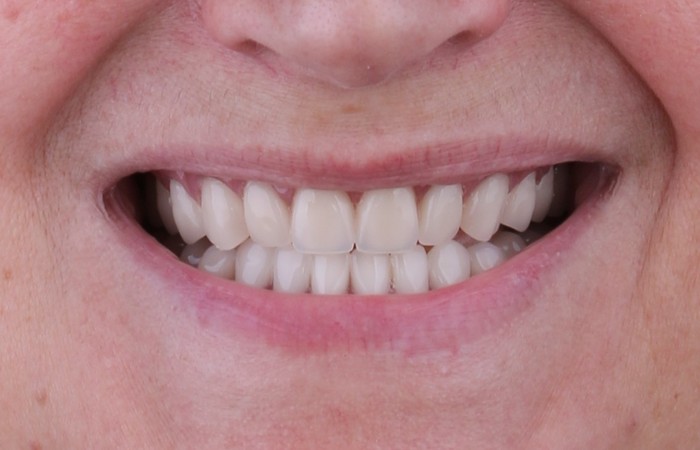

До и после удаления

Временный съемный протез, примеренный сразу после удаления зубов